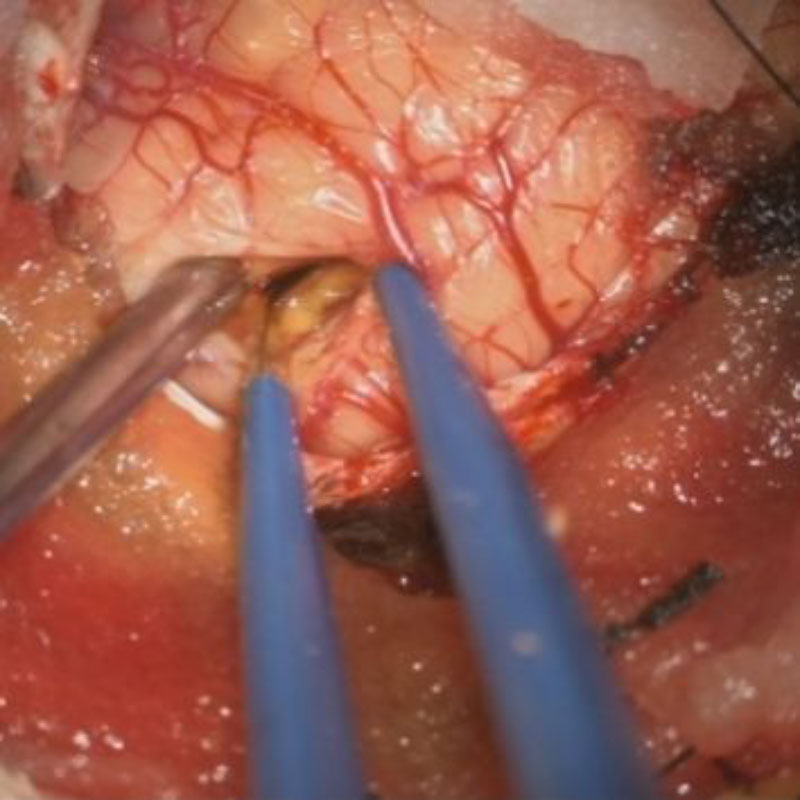

症例 '25年10月

No.

673

小脳腫瘍

頭蓋内腫瘍摘出術

手術前

1

手術前2

手術後